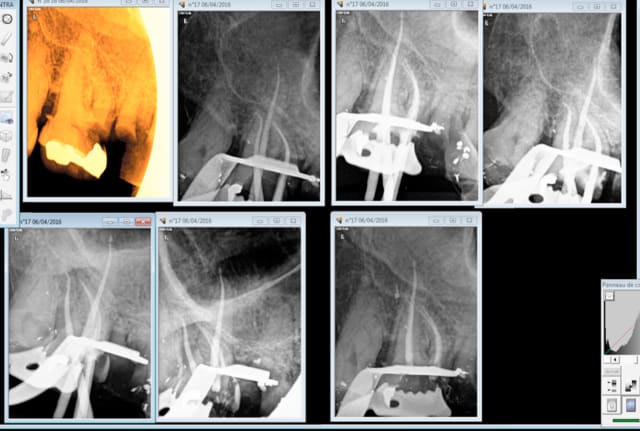

Tu vois moi aucune formation en endo ( en dehors de ma formation initiale mais qui n'est pas Roumaine par contre) , je ne fais que des merdes je roule en Porsche et je n'ai aucun souci. -)

A propos de l'endo c'est plus rapide en rotation continue à fond sur un contre angle bague bleue.

Capture d e cran 2016 04 06 14.20 - Eugenol

Capture d e cran 2016 04 06 14.22 - Eugenol